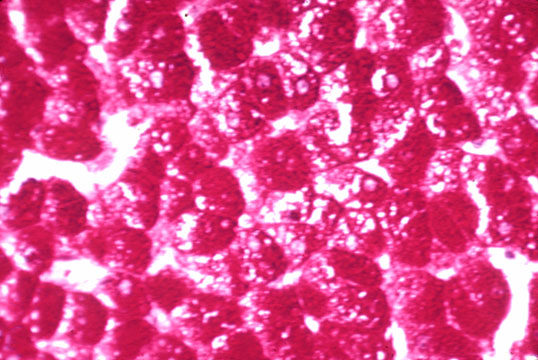

Intracytoplasmic inclusions with ground-glass appearance affecting most ...

Storage cells. Pre- and post-digestion with saliva for 2 weeks. Upper ...